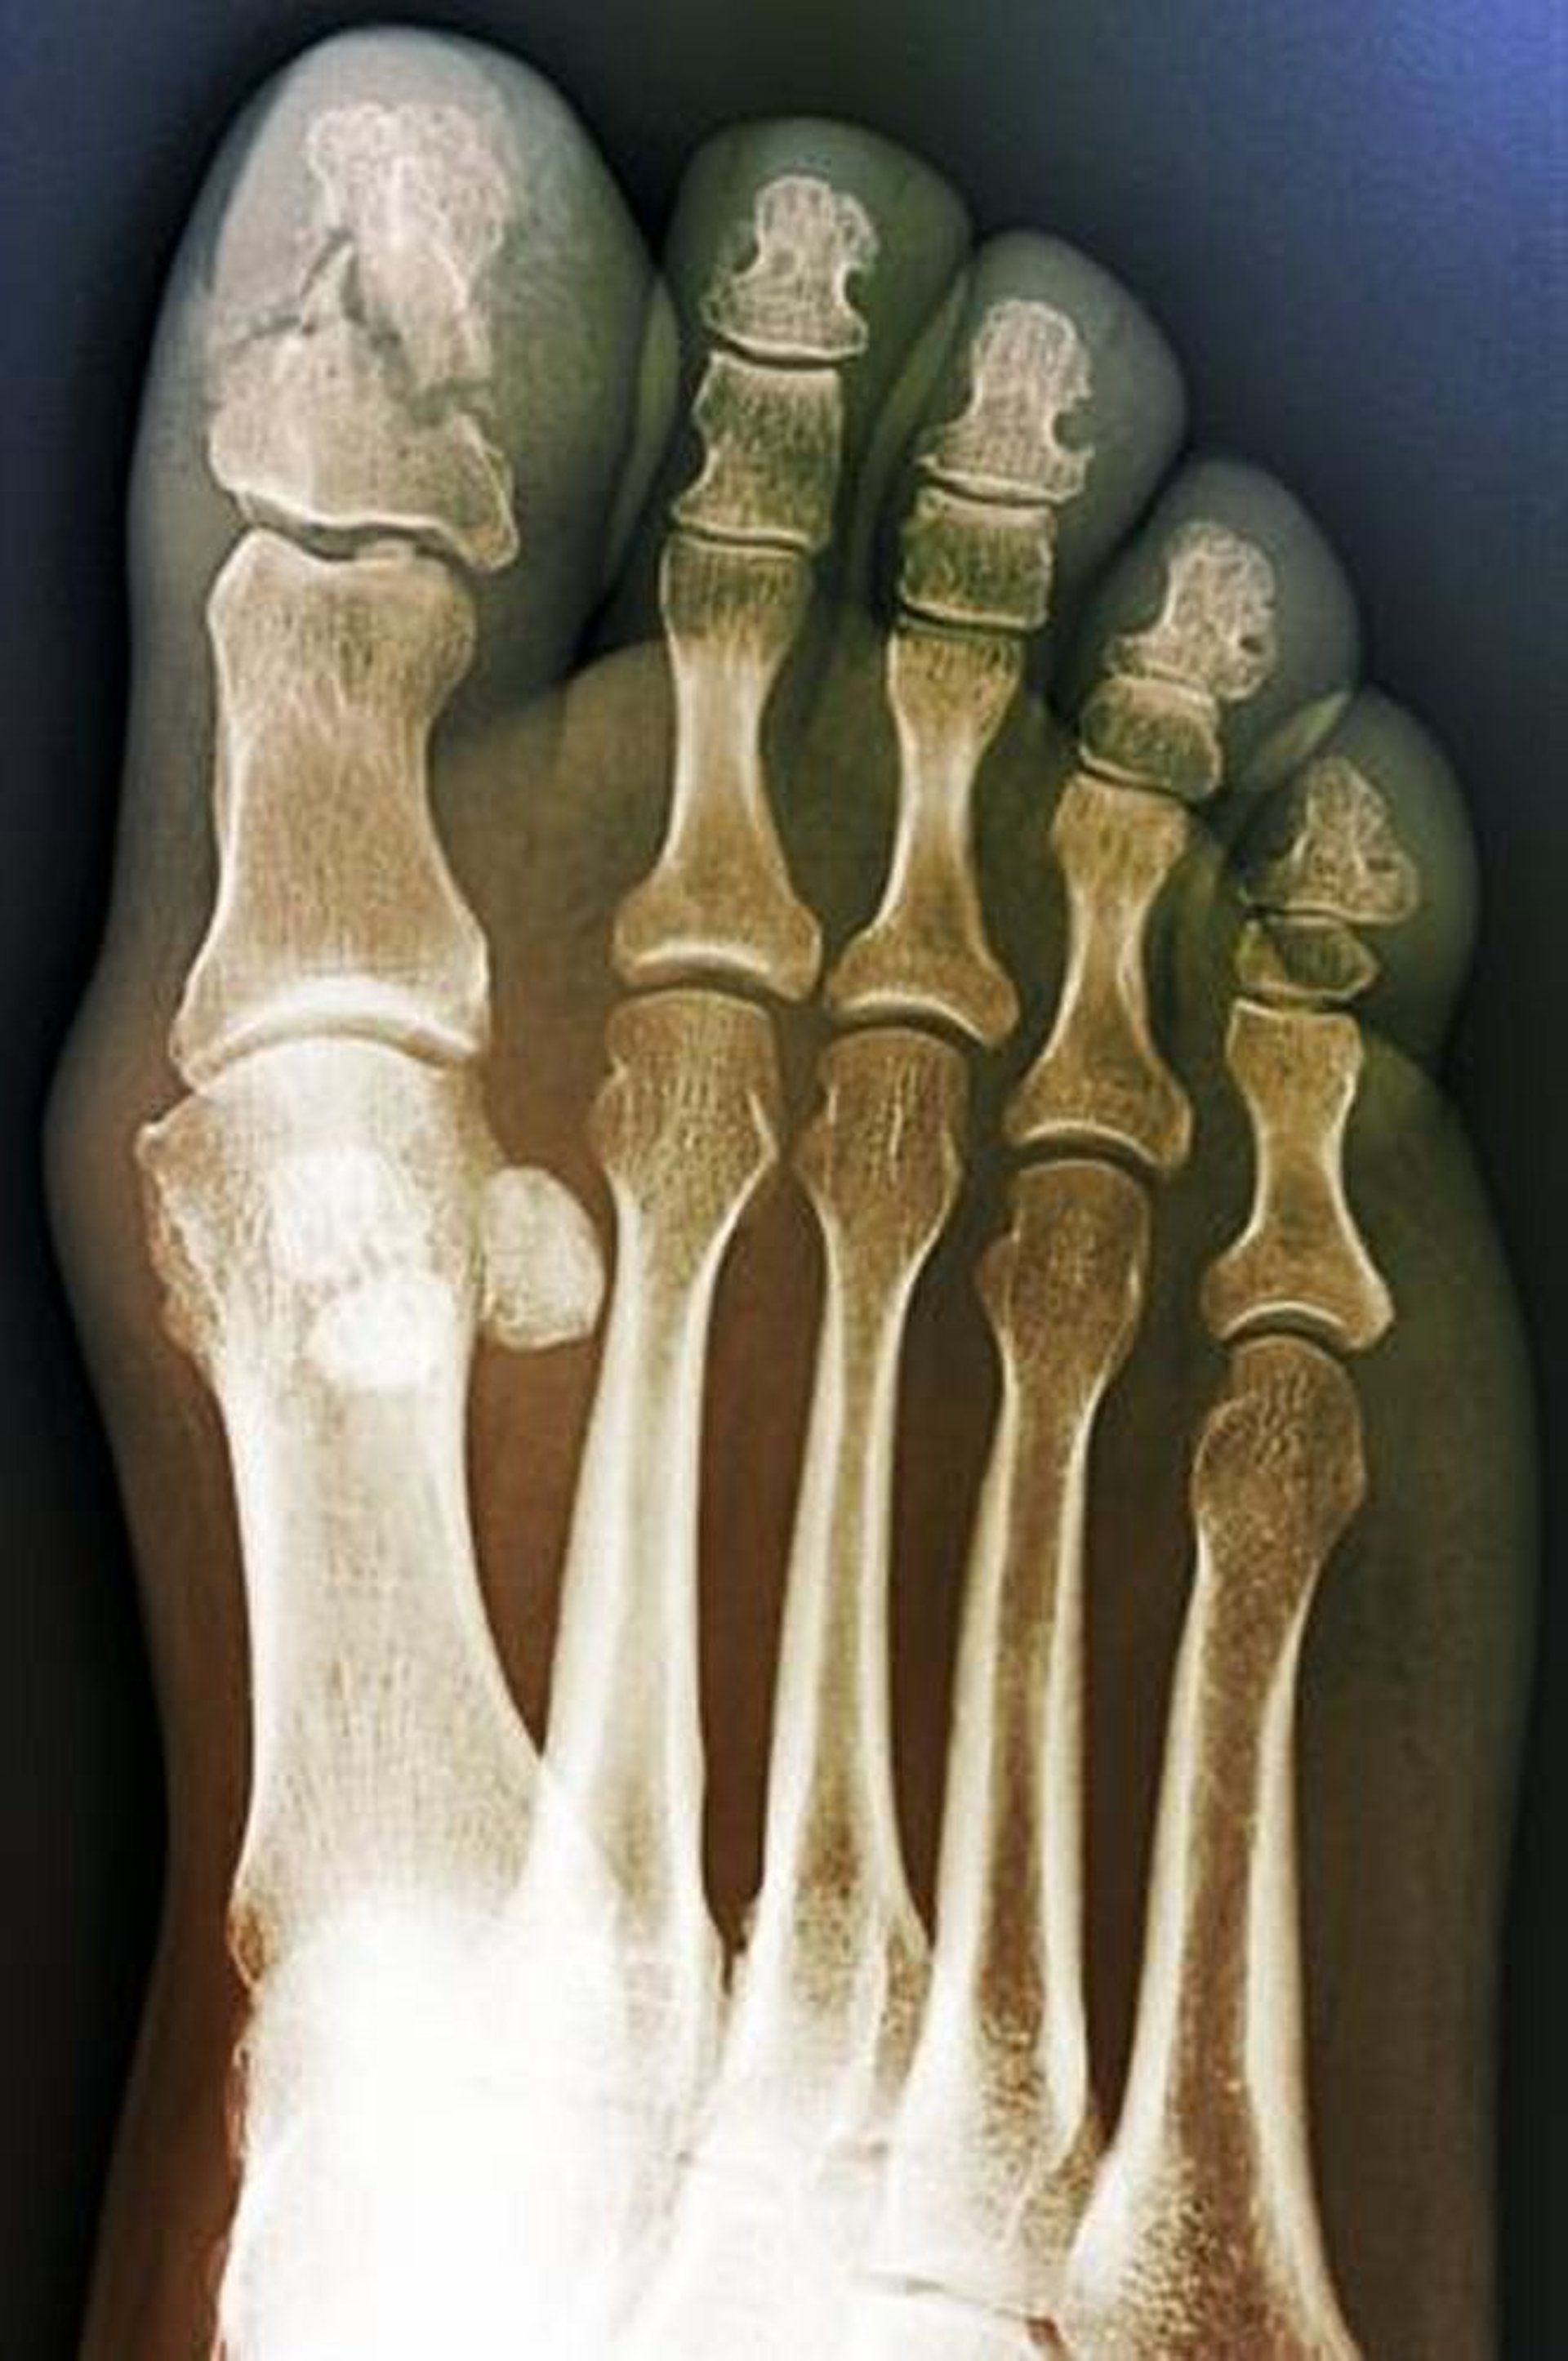

Fracture comminutive du gros orteil

Cette vue antéropostérieure (de face) montre une fracture comminutive de la phalange distale du gros orteil. Ce signe fait évoquer un mécanisme d'écrasement.

ZEPHYR/SCIENCE PHOTO LIBRARY